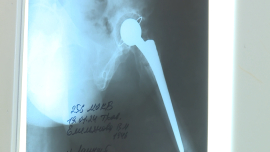

Операции эндопротезирования суставов отечественного производства проводят в Могилеве

Операции эндопротезирования суставов отечественного производства проводят в Могилеве от 25.04.2024